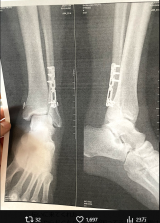

- 術後のレントゲン写真(@dr55634)